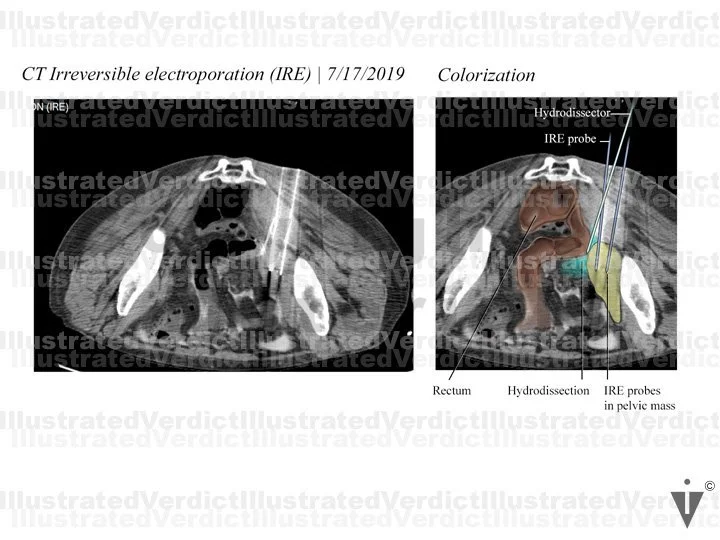

A 78-year-old woman with a history of infiltrating endometriosis presented with persistent, chronic pelvic, back, and flank pain. An MRI revealed a right-sided pelvic endometrioma mass, which encapsulated the right ureter and involved her pelvic nerves. She had a stent placed in the right ureter, and unfortunately, the pain increased. She underwent a CT-guided IRE as treatment. Post treatment, she felt pain in her right foot extending up her calf, and she experienced limited feeling in her right toes, foot, or ankle. A month after the procedure, her right pelvic, back, and flank pain had resolved, but she continued to have right leg paresthesia (pins and needles with numbing sensation). Unfortunately, nerve damage was a risk of the procedure. The jury found in favor of the defense.